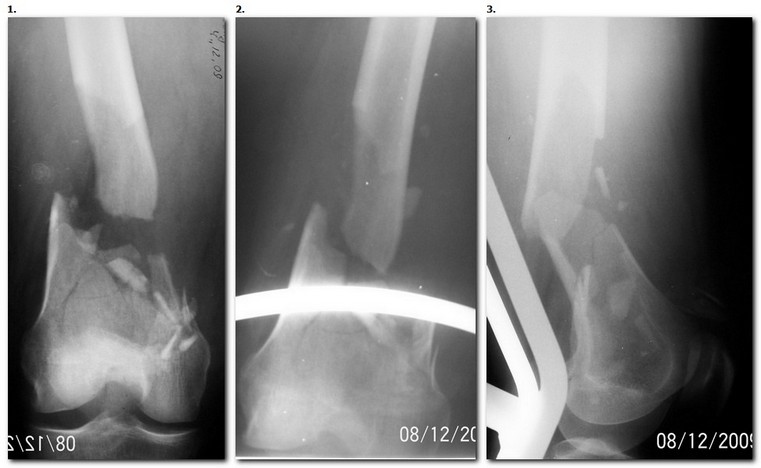

1. Открытый с дефектом кости 5 см оскольчатый внутрисуставной перелом дистального эпиметафиза бедренной кости. Величина дефекта установлена после сравнительных рентгенограмм обоих бёдер с линейкой. При поступлении выполнена ПХО раны, скелетное вытяжение за бугристость большеберцовой кости.

2. После долгих сомнений выполнена открытая репозиция перелома эпифиза бедренной кости, закрытый блокированный интрамедуллярный остеосинтез (к слову, оперативное вмешательство выполнено без применения ЭОПа). Предполагалась через 8 недель пластика костного дефекта спонгиозным аутотрансплантатом.

3. Снимок через 10 недель после операции. Имеется облаковидный регенерат. Решено от костной пластики воздержаться.

4. Через 6 месяцев имеем сросшийся перелом.

Безусловно, так бывает не всегда. Но, что касается показаний к костной пластике, такой вариант развития событий надо иметь ввиду.